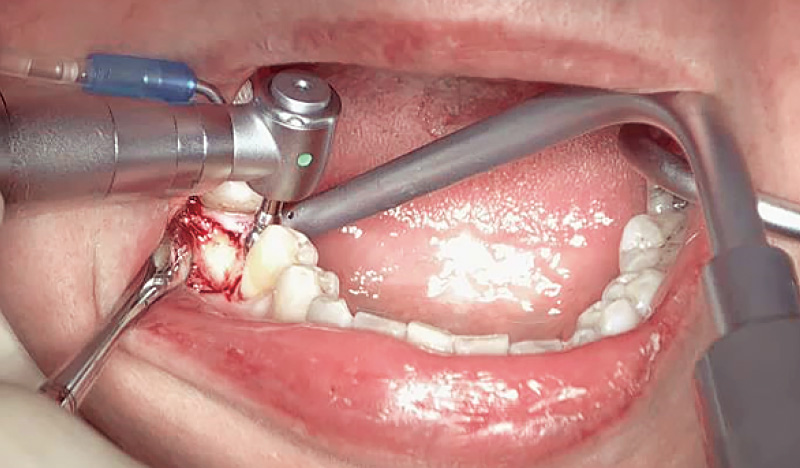

症例1-3 インプラント埋入部位の歯肉を切開。(「ル -

症例1-4 顎骨を露出させ、ドリリング後にインプラントを埋入。(「ルナビューショット」で撮影した動画より抽出) -